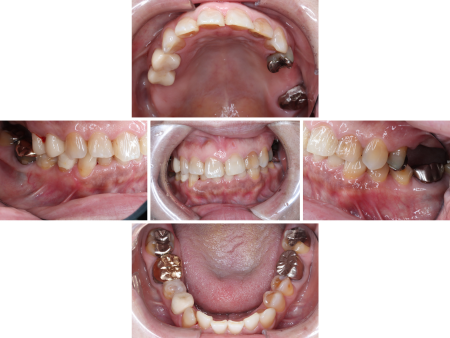

その後、下の被せ物治療を開始しました。最初に被せ物装着後のお口の中を再現するために模型を作製し、入れ歯を入れる高さが十分に確保され下の歯に当たらないことを確認後、下の歯12本(右下第2大臼歯〜左下第2小臼歯)に順次被せ物を作製・装着して噛み合わせの高さを上げていきました。

被せ物は自然な白さで耐久性もある「ジルコニアクラウン」を採用しています。

最後に上の部分入れ歯として、適合がよく装着時の違和感が少ない「金属床義歯」を作製し、治療を終了しました。